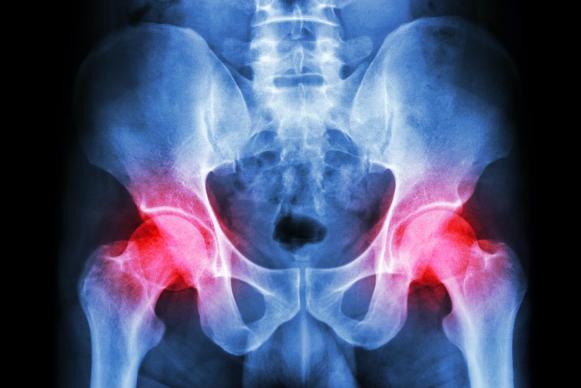

3. Hip Osteoarthritis

Osteoarthritis is the wear and tear of a joint that occurs

over time. This wears away the cartilage in the joint, which leads to bone

rubbing on bone when you move your hip. Hip osteoarthritis is more common in

older adults. Pain starts gradually and is deep and aching. Over time, the pain

may become constant. Your hip may be stiff. It may grate, lock or stick. The

pain in your hip may get worse with activity and feel worse in the morning. If

you have hip pain that has gradually increased over time, call your doctor for

an evaluation.

4. Hip Inflammatory Arthritis

A different type of arthritis happens when your body’s

immune system malfunctions and attacks your joints. This arthritis usually

starts at a younger age than osteoarthritis. The most common example is

rheumatoid arthritis. You may have hip pain and stiffness along with other

symptoms, like fever and fatigue. You may feel pain in both hips and in other

joints, too. Pain may ease after you get out of bed in the morning and start

moving. These are all signs to see your doctor.